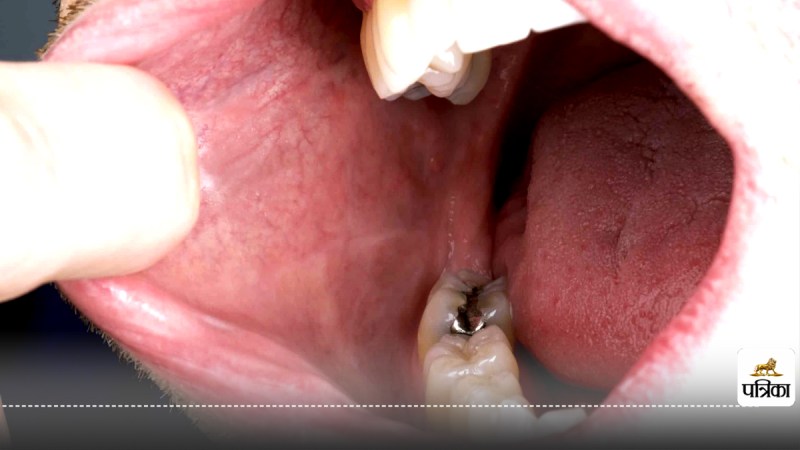

अतीत में, मुंह का कैंसर (Muh ka cancer) मुख्य रूप से तंबाकू, शराब और सुपारी के सेवन से जुड़ा माना जाता था और आमतौर पर बुजुर्ग पुरुषों में देखा जाता था। लेकिन अब, धूम्रपान करने वालों की संख्या घटने के बावजूद, यह बीमारी कम उम्र की महिलाओं में तेजी से बढ़ रही है, जो ना तो धूम्रपान करती हैं और ना ही शराब का सेवन करती हैं।

साल 2020 में, विश्वभर में 3,55,000 से अधिक नए मामले सामने आए, जिसमें से लगभग 1,77,000 मौतें इस बीमारी के कारण हुईं। सबसे चौंकाने वाली बात यह है कि यह बीमारी अब गैर-धूम्रपान करने वाले लोगों में भी बढ़ रही है, खासकर युवा श्वेत महिलाओं में।

वैज्ञानिकों का मानना है कि इस तेजी से बढ़ते खतरे के पीछे आहार एक प्रमुख भूमिका निभा सकता है। अभी तक मुंह के कैंसर (Oral cancer) के बढ़ते मामलों के पीछे एचपीवी संक्रमण (मानव पैपिलोमा वायरस) को जिम्मेदार माना जा रहा था, लेकिन हालिया अध्ययन में एचपीवी को इसकी वजह मानने से इनकार कर दिया गया है।